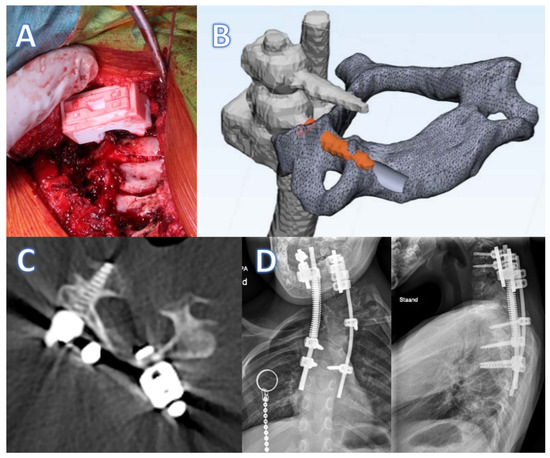

3. Device Description of Click-on Pedicle Guides

6. Device Description of Spinal Prosthesis

6.2. Design

Implant Production

6.3. Clinical Experience with Spinal Prosthesis